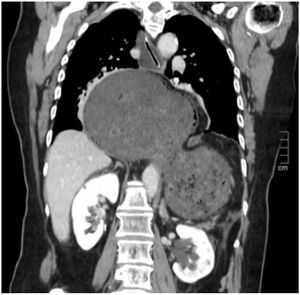

A 78-year-old woman consulted for epigastric abdominal pain of 24 h' duration. Thoracoabdominal CT scan showed evidence of giant hiatus hernia complicated by gastric volvulus (Fig. 1). After CT scan, cardiorespiratory arrest secondary to obstructive shock due to cardiac tamponade. The patient was successfully resuscitated and gastroscopy was performed, identifying gastric ischaemia with areas of necrosis, for which urgent surgery was indicated. After gastric reduction and devolvement, extensive necrosis was found in the greater curvature. Vertical gastrectomy, closure of diaphragmatic pillars and feeding jejunostomy were performed.

Case study diagnosis: hiatal hernia complicated by gastric volvulus.